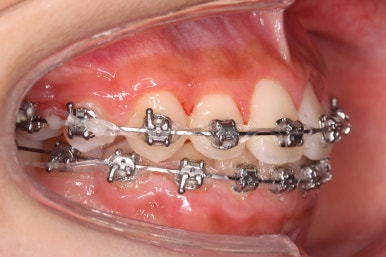

처음 내원 때의 입안 모습입니다.

영구치는 모두 맹출이 되어있었고 아랫니는 윗니에 비해 매우 가지런한 편이였습니다.

윗니 중에서도 앞니가 매우 삐뚤하고 특히 작은 앞니 양쪽 모두가 아래 앞니보다 안쪽에 들어가 있는 모습입니다.

이번 환자분은 송곳니가 거의 자기위치에 나오게 되면서 약한 작은 앞니를 밀어낸 경우입니다.

송곳니는 거의 제자리에 나오긴 했지만 작은 앞니가 안쪽으로 쏙 들어가 있기 대문에 상대적으로 덧니처럼 보이게 되는 것입니다.